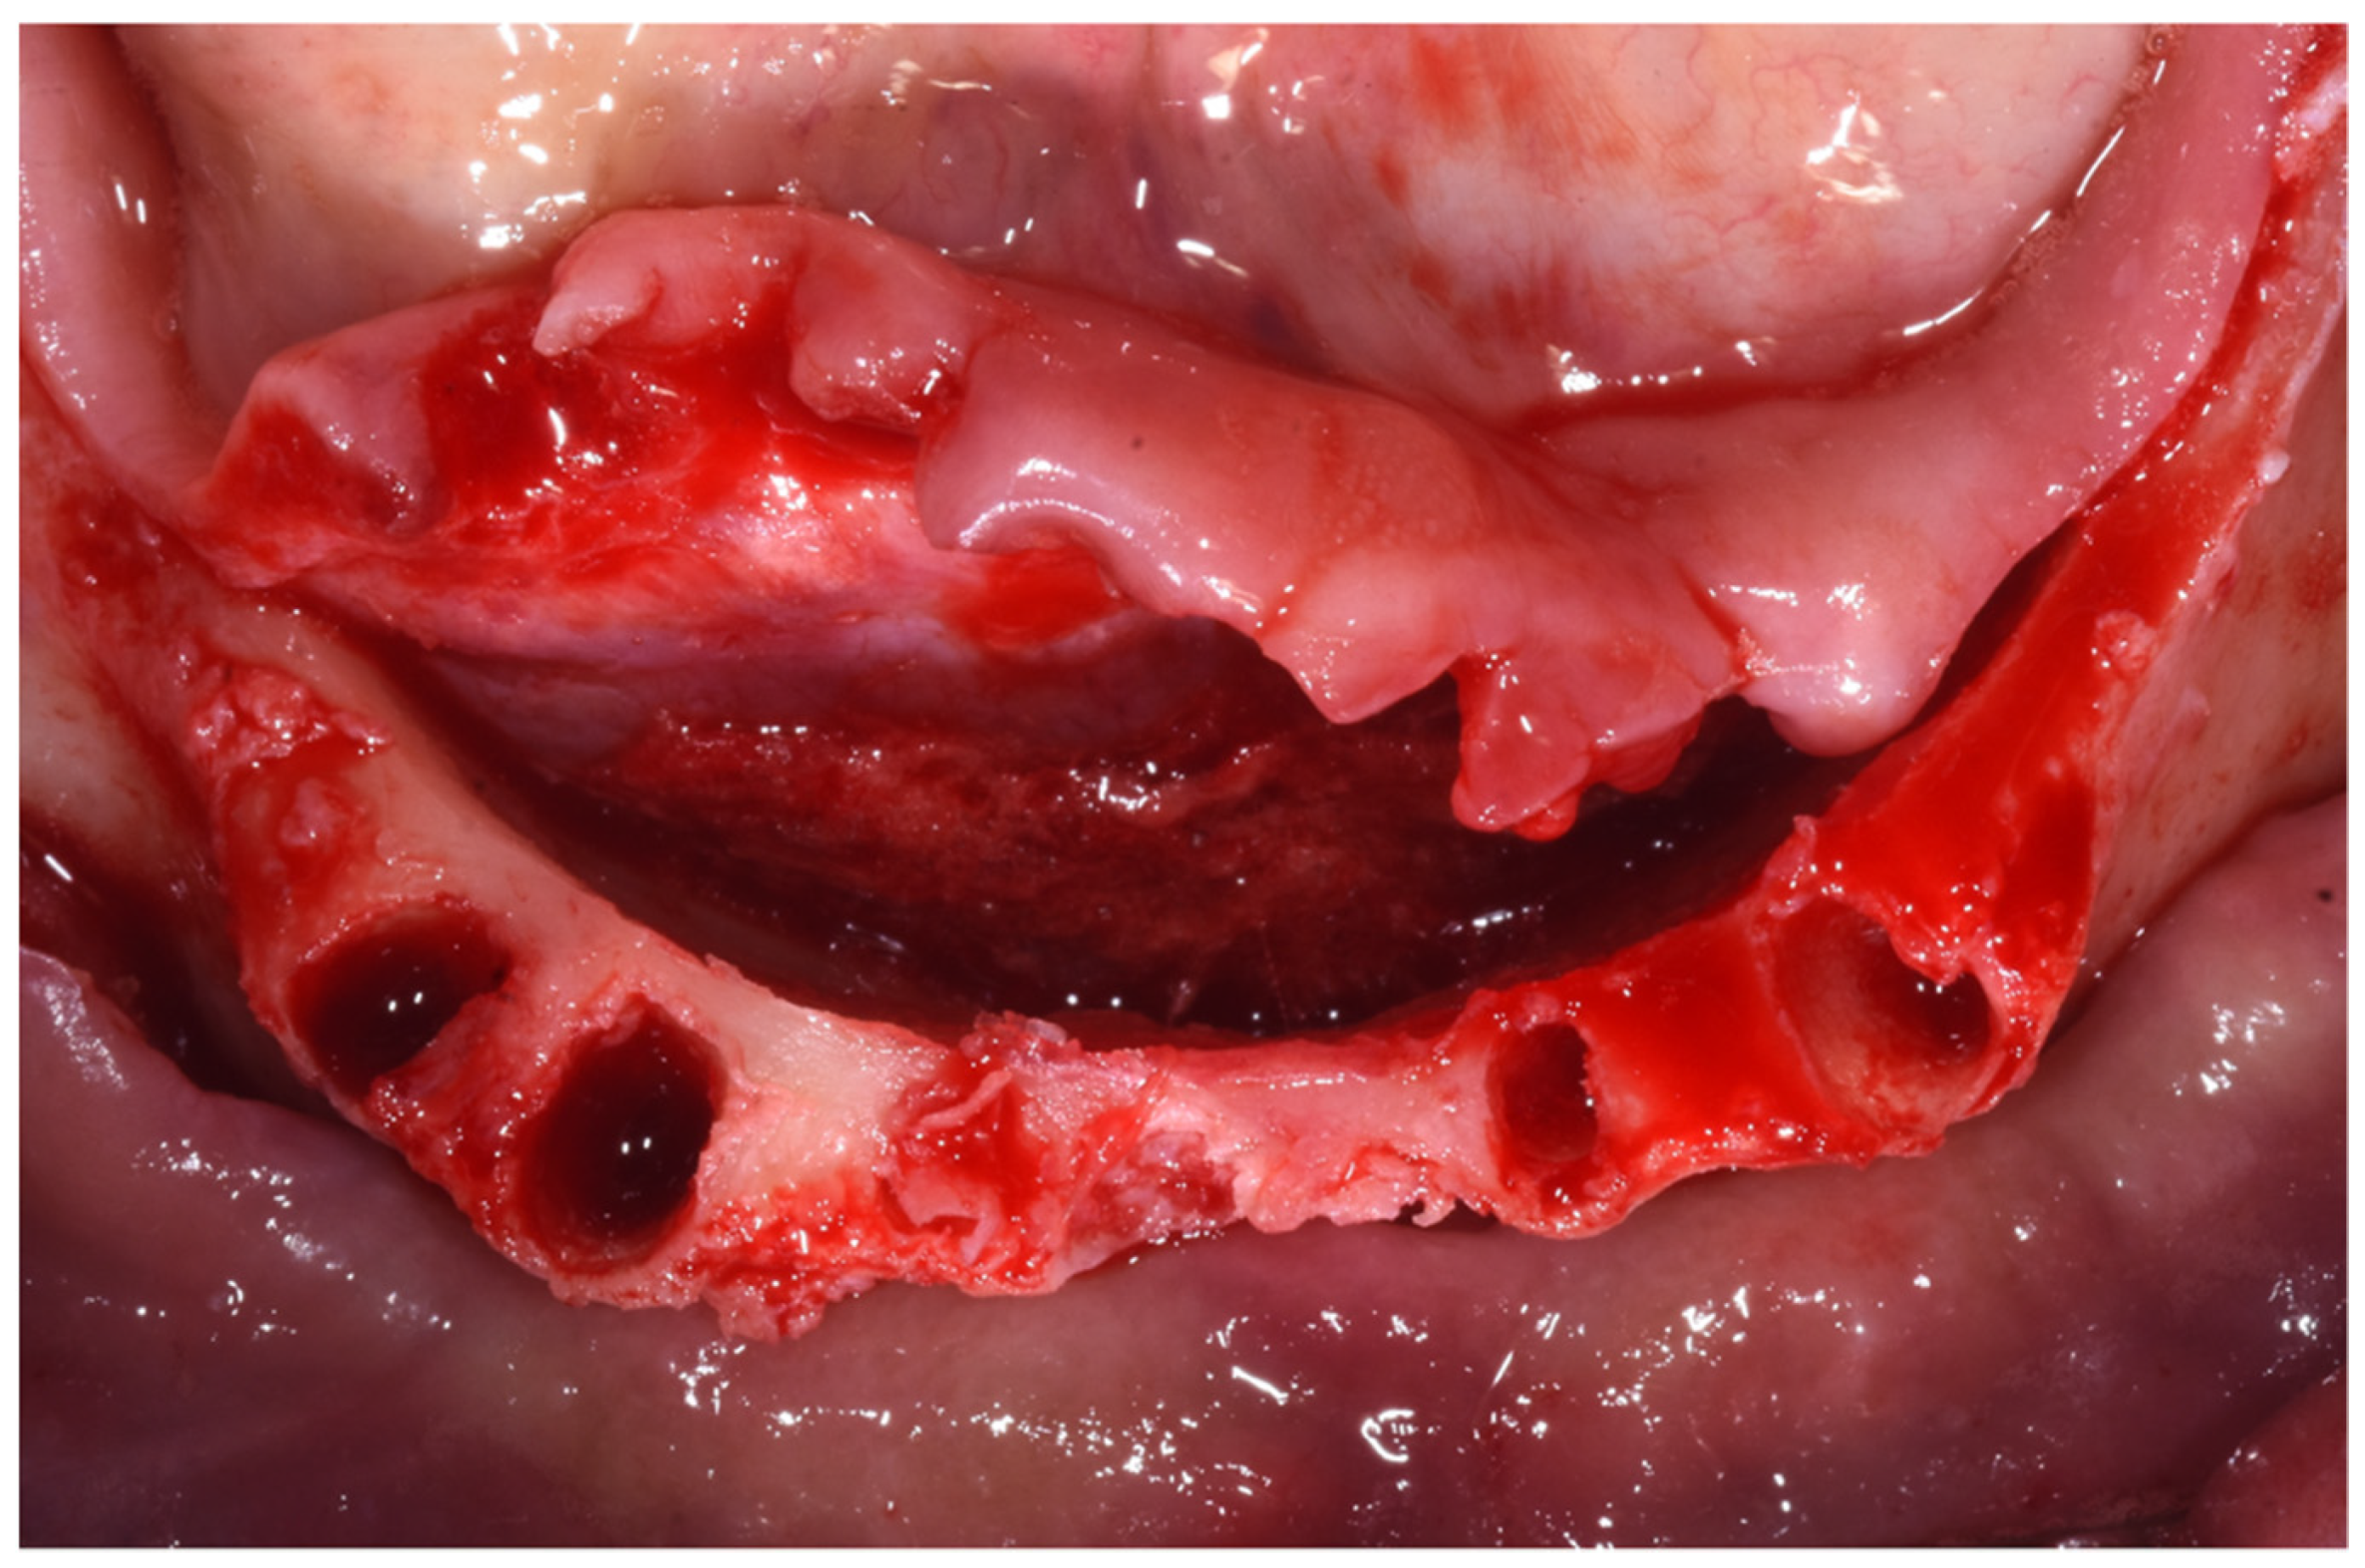

Surgery Appointment